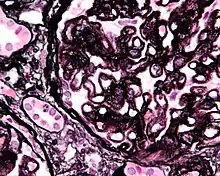

Renal corpuscle (glomerulus) showing glomular basement membrane.

Renal corpuscle (glomerulus) showing glomular basement membrane.